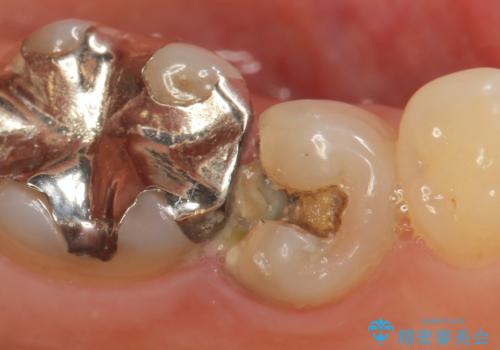

ラミネートベニヤの破折 ジルコニアクラウンによるやり替え

- 欠けてしまった前歯のラミネートベニヤと見た目の改善を求めて来院されました。

歯の大きさの不揃いと、虫歯の再発を認めたためラミネートのやりかえではなく一挙に問題の解決のできるジルコニアクラウンでの治療を計画します。